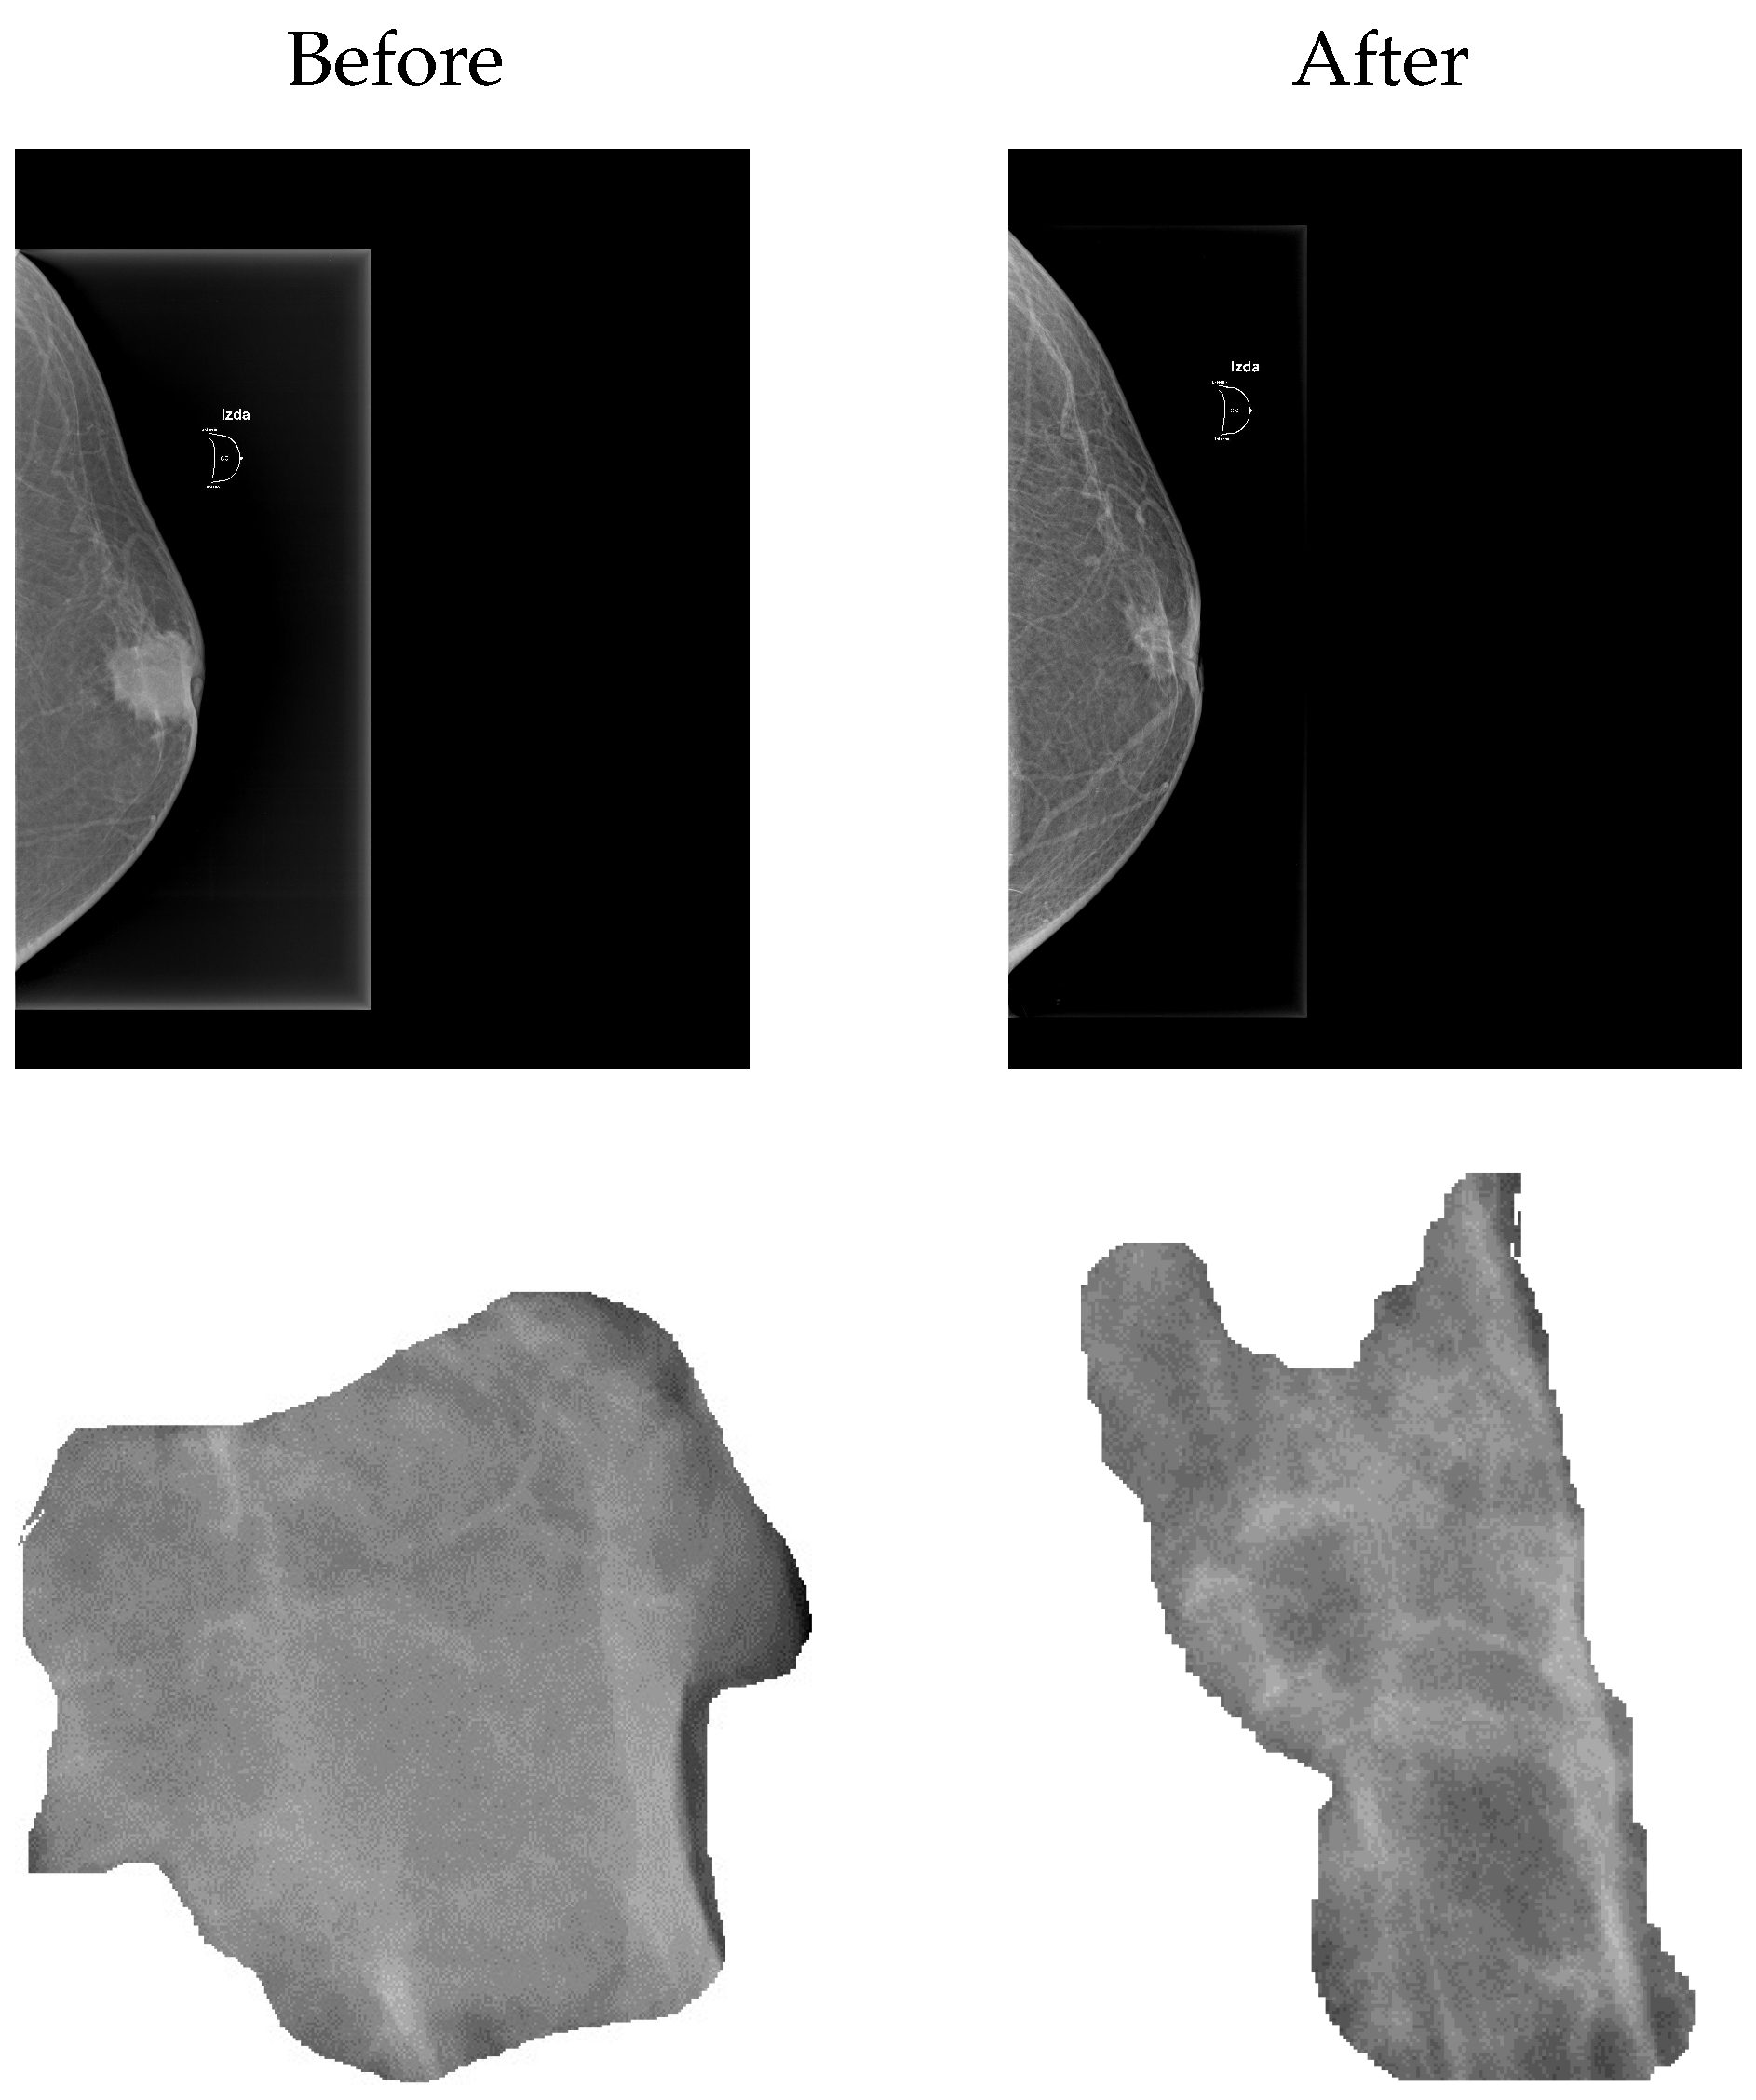

2.2. Mesoscopic Technique